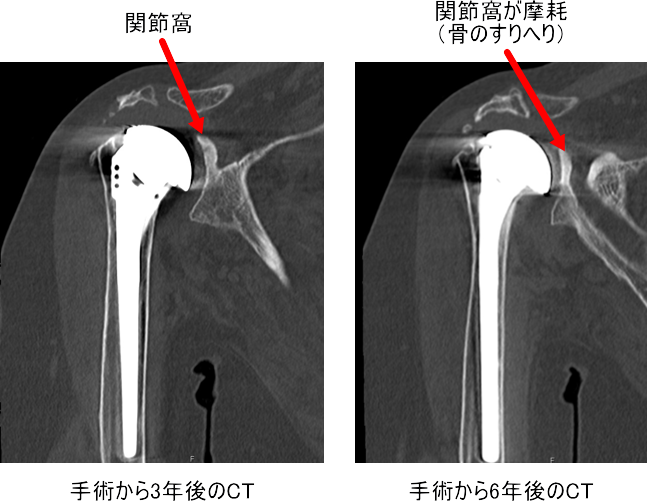

75歳 女性 右肩

以前に変形性肩関節症で人工肩関節置換術を施行しています

CT でよくみると関節窩がすりへっています